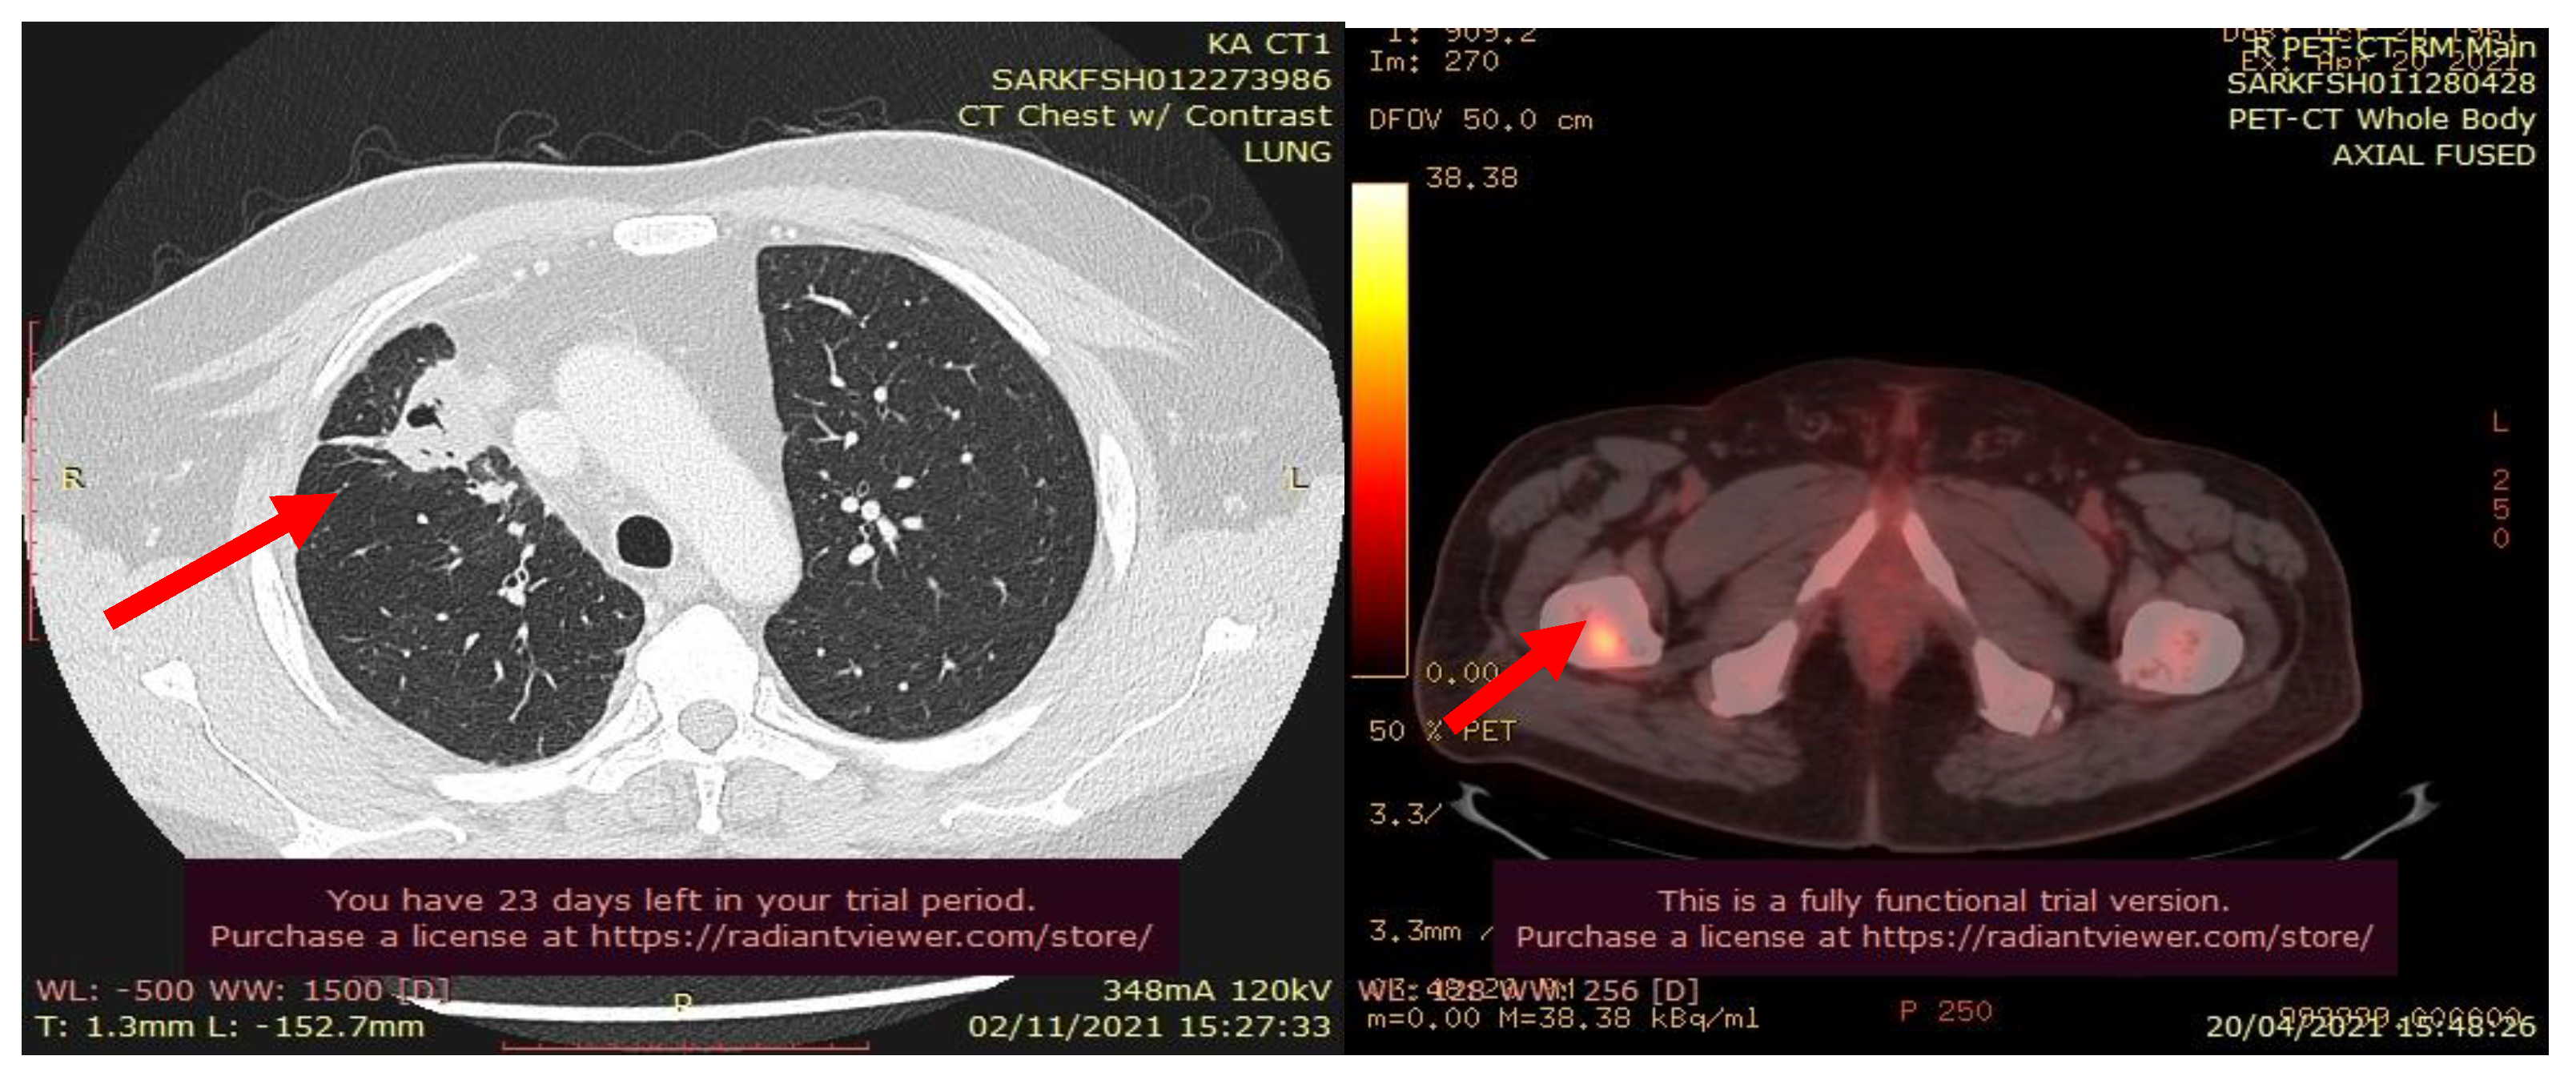

In July 2021, a 60-year-old patient came to our Cryosurgery unit, provided with a CT scan of the chest dated April 2021. The CT scan revealed the presence of a hyper-metabolic lesion with a size of 2.8 cm and involving the right upper/middle lobe related to the neoplastic process. The presence of hypermetabolic lytic bone lesions involving the right proximal femur T-10 and the left transverse process of T-9 was also confirmed, highlighting bone metastasis (Figure 4).

Figure 4. CT scan (left) and Pet- CT (right) images from April 2021 with evidence of bone metastases. The arrows indicate the tumor’s location.